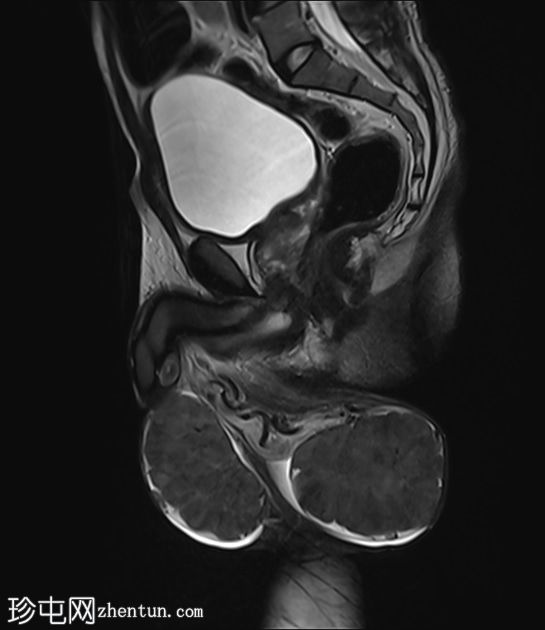

矢状位

T2加权像

阴囊内睾丸增大,T1加权像上可见分叶状软组织病变,呈中高信号,T2加权像上呈低信号。

轻度双侧鞘膜积液。

本病例表现为双侧睾丸肿胀,影像学特征符合睾丸肾上腺残余肿瘤的典型表现,即T1加权像上呈双侧中高信号,T2加权像上呈低信号。